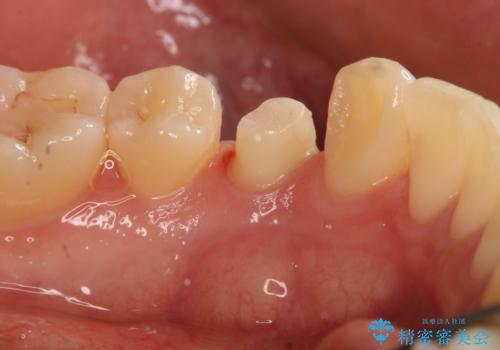

- 左下4番のう蝕を指摘され治療を希望された患者様です。

切削量などを考慮しクラウンでの治療を提案したところ、セラミックを希望されたのでフルジルコニアクラウンでの治療を選択しました。

う蝕が深かったので痛みが出る可能性をお伝えしましたが特に症状は現れなかったので、予定通りセラミッククラウンでの治療を行いました。